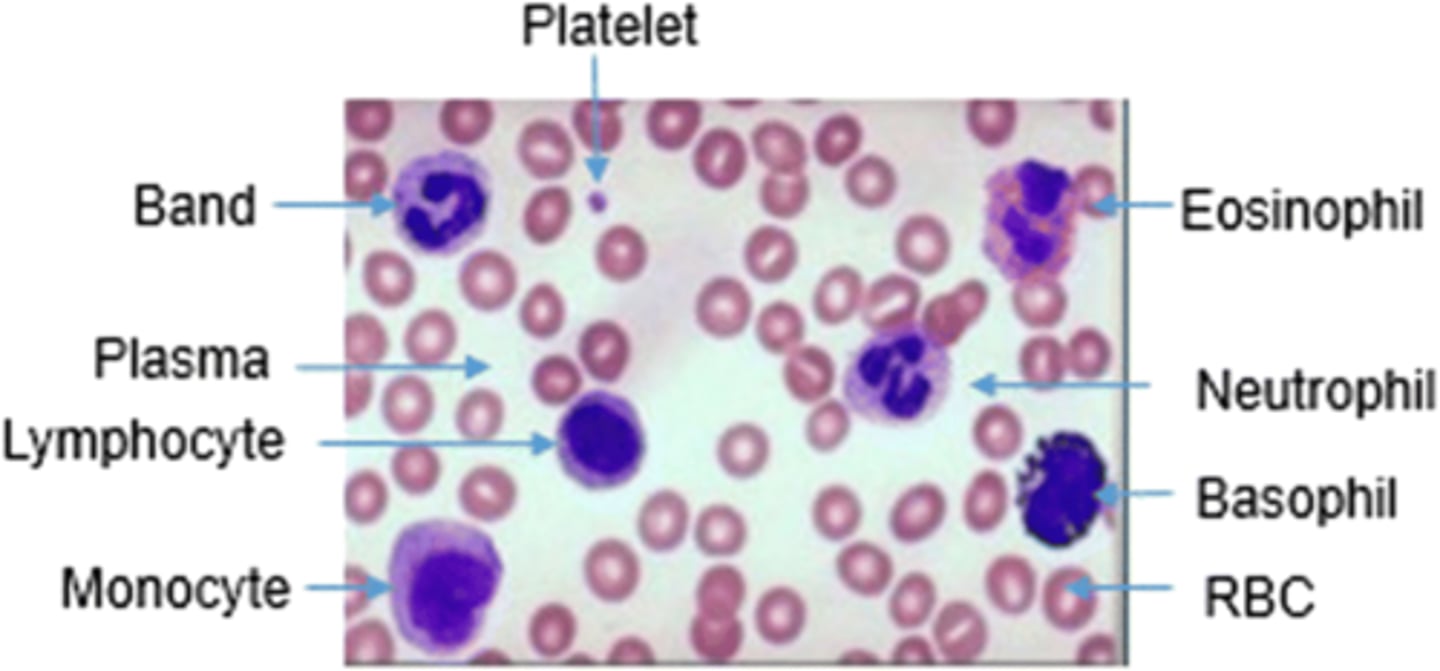

how do you distinguish between a monocyte and lymphocyte under a microscope?

monocyte has a kidney bean nucleus, lymphocyte have a large nucleus that takes up most the cell